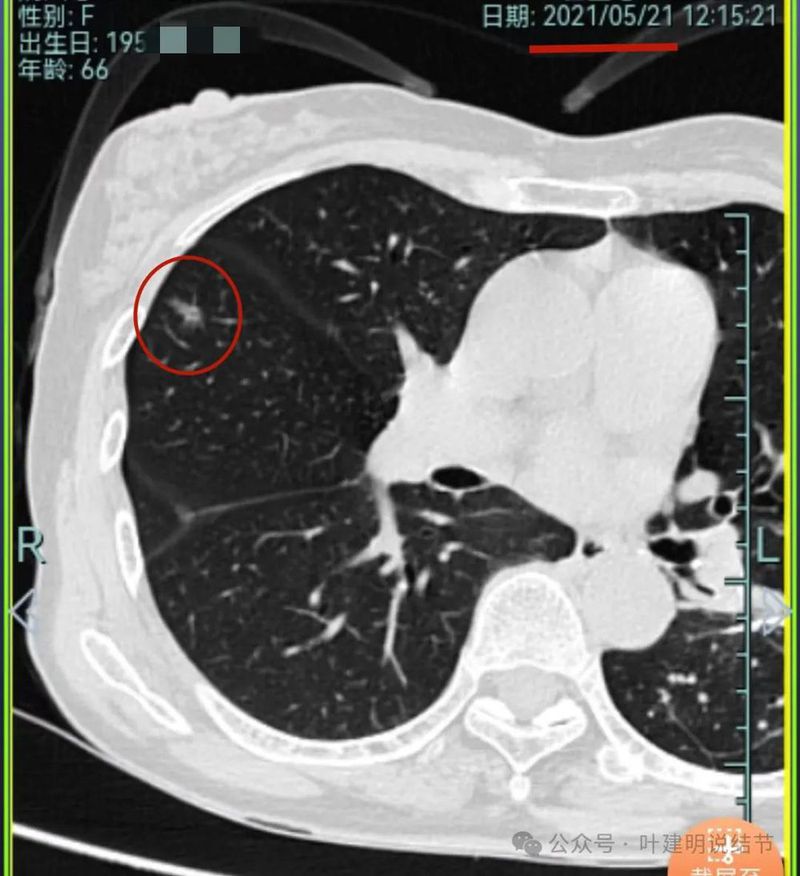

再看2021年随访的影像:

病灶1似乎中间高密度部分略有密度增高。

病灶2与2019年时相仿。

病灶3仍是混合密度,进展不显著。

病灶4仍是伴钙化的,也没有明显进展。

病灶5较前密度略显杂乱,整体密度应该有所增高。

病灶6轮廓较前清楚,灶内有血管穿行,也有轻微胸膜牵拉。

原病灶7已经被切除。